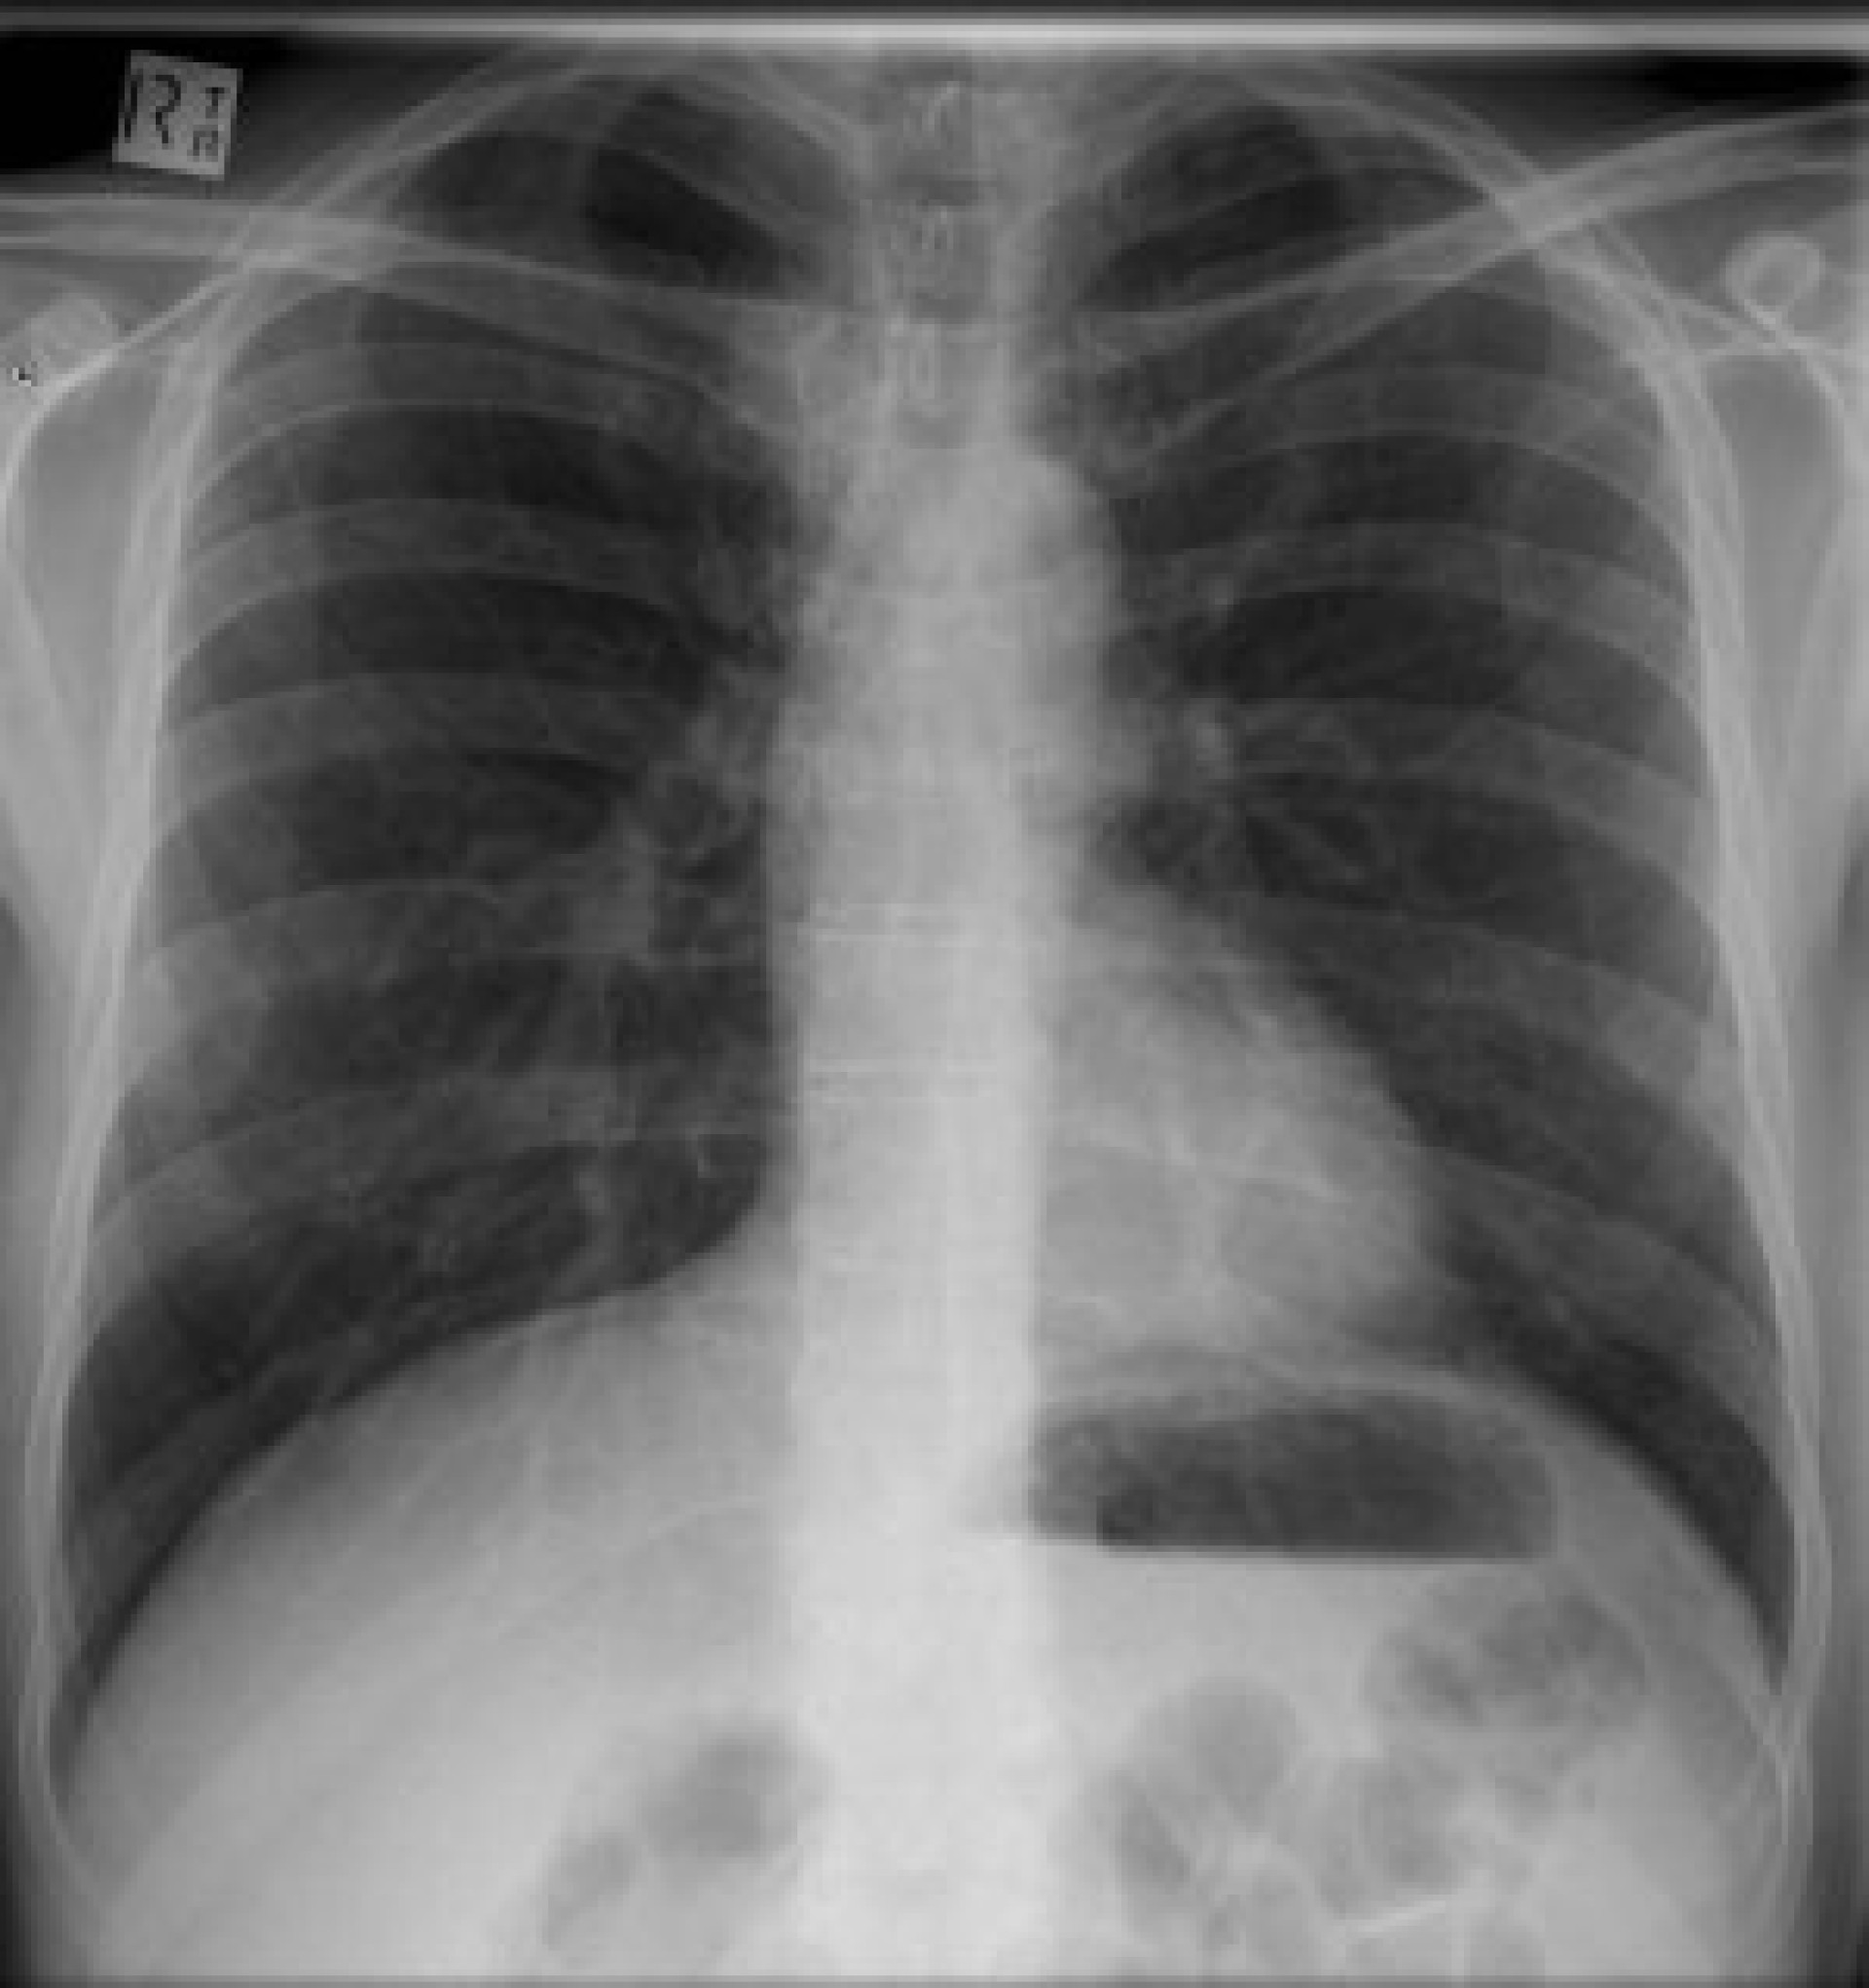

Лекари от болницата \"Св. Анна\" в столицата станаха свидетели на нечувана диагноза. Леля Попова (53) отишла на рентгеновата машина, след като се оплакала от поглъщане на четири пакета шивашки копчета от по 15 броя във всеки. Жената ги погълнала с чаша студен чай, мислейки ги за вълшебни хапове за връщане на линията на талията, когато е била на двадесет.

Рентгенологът Коста Монооков останал учуден, когато костите на жената се оказали извити, а ставите й пълни с евкалиптово желе. Проверил в няколко медицински енциклопедии и в интернет и се шашнал: диагнозата била брюкселиоза, болест, срещана изцяло във вида на коалите - двуутробни същества от Австралия.

Но когато Коста Монооков направил тест на рентгеновия си апарат, за да настрои светкавицата, той отново видял костите, без Леля Попова да е пред машината. Оказало се, че токът в болницата \"Св. Анна\" бил малко по-силен от необходимото и апаратът стигал чак до другата страна на Земята, снимайки коала резерват в Източна Австралия.